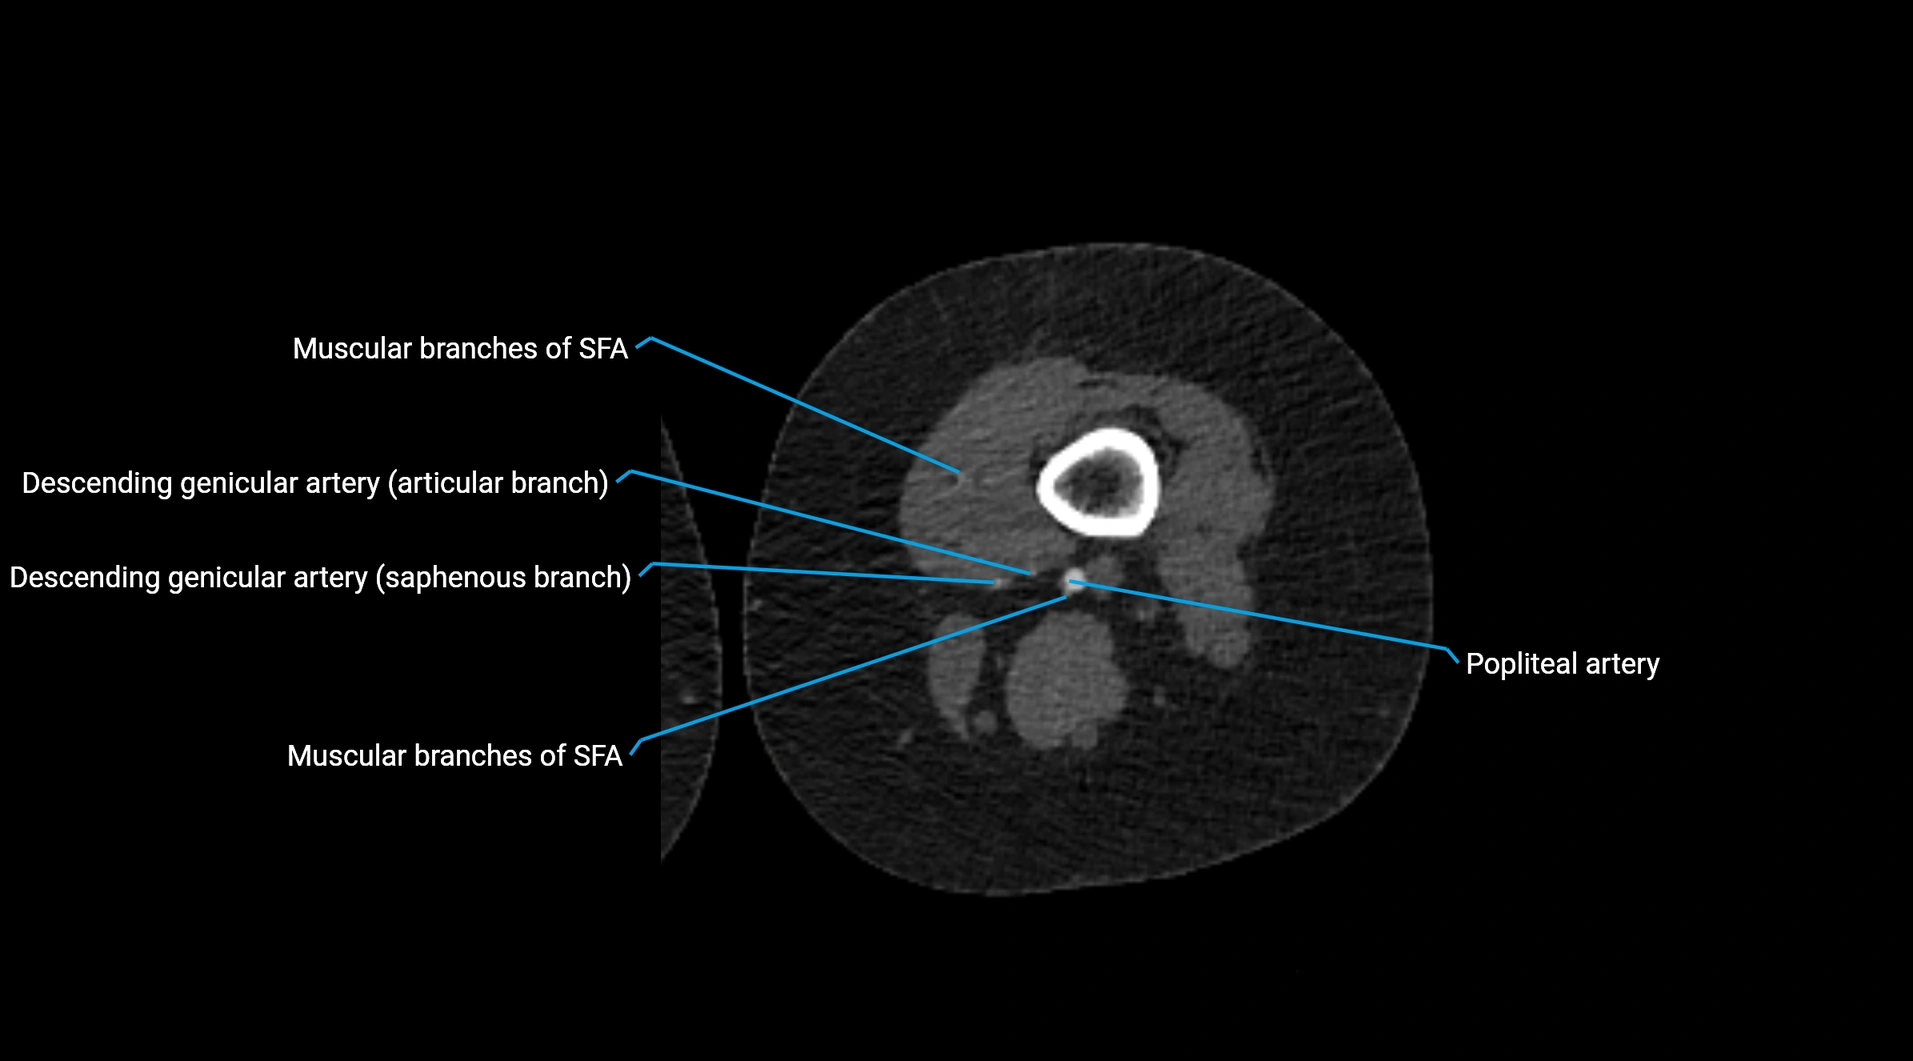

CT images

image

Contrast-enhanced CT (CTA):

• Gold standard for abdominal aortic imaging

• Provides excellent detail of lumen, wall, aneurysm, thrombus, and branch vessels

• Multiplanar and 3D reconstructions help in aneurysm measurement, stent graft planning, and dissection evaluation